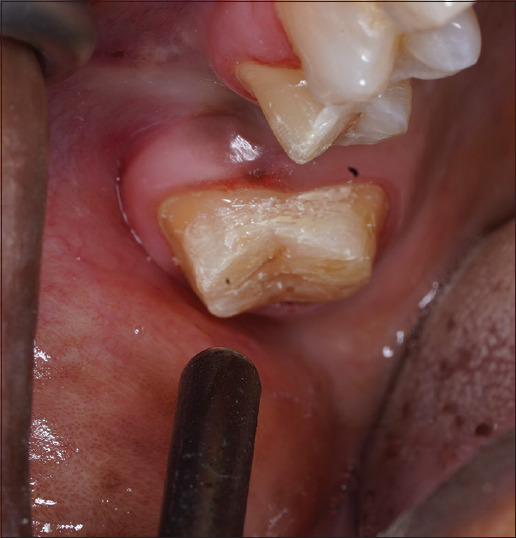

Materials and methods: 39 participants of age 25-30 years requiring vital tooth preparation were divided into Group A as control, distilled water as placebo; Group B test control, 7th generation dentin bonding agent; and Group C test, bioactive glass. Dentin hypersensitivity was evaluated on the day of preparation (T0), 7th day after preparation (T1), and 15th day (T2) at the final cementation procedure using the Schiff scale.